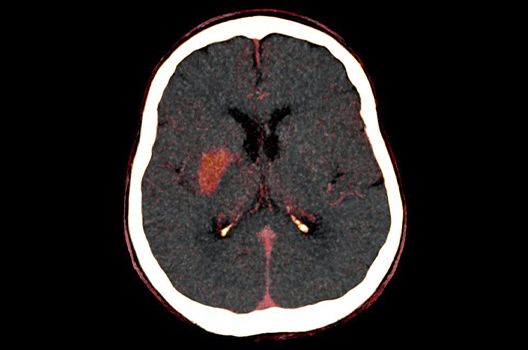

Computertomographie

- Dosis- und Artefaktreduktion

- CT-Bildnachverarbeitung

- Quantitative und automatisierte CT-Bildanalyse

Die Schwerpunkte in der CT-Forschung liegen in der Bildnachverarbeitung, der Dosis- und Artefaktreduktion sowie der quantitativen und automatisierten CT-Bildanalyse.

Die Computertomographie (CT) ist ein Verfahren, bei der mit Hilfe von Röntgenstrahlung Schnittbilder des Körperinneren angefertigt werden. Unser Bestreben ist es hierbei, bei möglichst niedriger Strahlendosis eine bestmögliche Bildqualität zu erzielen. Eine zunehmend große Rolle in der radiologischen Forschung spielen zudem die Automatisierung in der Bildanalyse und die computergestützte Auswertung großer Datenmengen, wie sie bei einer CT-Untersuchung anfallen. Wir arbeiten in enger Kooperation mit den Geräteherstellern zusammen und sind daher maßgeblich an der Entwicklung und Erprobung neuer Techniken beteiligt.

- Moderne Methoden der Schlaganfalldiagnostik und -therapie